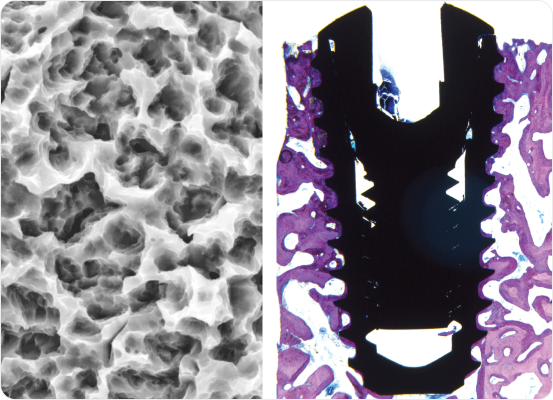

S.L.A. surface treatment (sandblasted and acid-etched) enhances osseointegration and long-term stability.

(Sandblasting with large grits and acid etching)

Well documented and clinically proven surface technology.

Reference: Myron Nevins, et al., :”Clnical and Histologic Evaluations of SLA Dental implants” Int J Periodontics Restorative Dent 2017; 37:175-181. dol: 10.11607/prd.3131